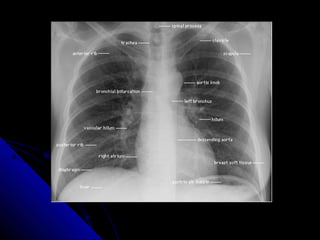

NNoorrmmaall AAnnaattoommyy

RRiibb((AAnntt/PPoosstt))

LLeefftt 22/RRiigghhtt 44

CCoossttootthhoorraacciicc rraattiioo

CCeennttrraall ttrraacchheeaa

HHiillaarr:: LLtt>>RRtt

LLuunngg ffiieelldd:: CCeennttrraall>> PPeerriipphheerraall/ PPeerriipphheerraall cclleeaarr

zzoonnee

PPlleeuurraa:: LLiinneeaarr

DDiiaapphhrraaggmm:: RRiigghhtt >>lleefftt/ AAnnggllee/GGaassttrriicc ppaatttteerrnn

SSuubbccuuttaanneeoouuss ttiissssuuee

NNoorrmmaall AAnnaattoommyy RRiibb((AAnntt/PPoosstt)) LLeefftt 22/RRiigghhtt 44 CCoossttootthhoorraacciicc rraattiioo CCeennttrraall ttrraacchheeaa HHiillaarr:: LLtt>>RRtt LLuunngg ffiieelldd:: CCeennttrraall>> PPeerriipphheerraall/ PPeerriipphheerraall cclleeaarr zzoonnee PPlleeuurraa:: LLiinneeaarr DDiiaapphhrraaggmm:: RRiigghhtt >>lleefftt/ AAnnggllee/GGaassttrriicc ppaatttteerrnn SSuubbccuuttaanneeoouuss ttiissssuuee 6